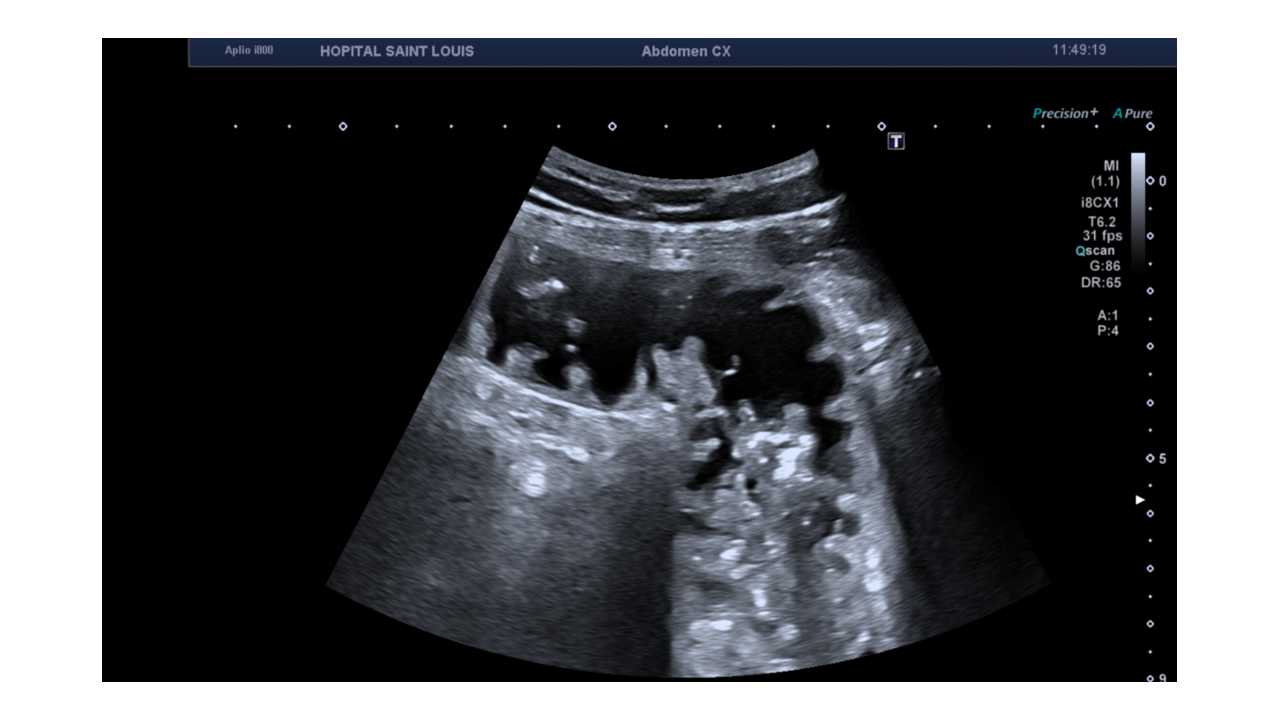

Apres avoir exploré les reins, la prostate (en sus pubien) et la vessie, son attention se porte sur cette image, à droite de la vessie sur une coupe sagittale, et sur l'ascite dans le cul de sac de douglas.

Le patient présente des douleurs abdominales, un balayage complémentaire est alors réalisé avec une fréquence d’émission augmentée pour mettre en évidence cette structure.

Une distension d'une anse grêle mesurée à 37mm de diamètre antéro postérieur est détectée.

Le diamètre d’une anse grêle ne doit pas dépasser 25mm .

Un apéristaltisme est ausi observé.